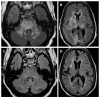

We describe common and less common diseases that can cause magnetic resonance signal abnormalities of middle cerebellar peduncles (MCP), offering a systematic approach correlating imaging findings with clinical clues and pathologic mechanisms. Myelin abnormalities, different types of edema or neurodegenerative processes, can cause areas of abnormal T2 signal, variable enhancement, and patterns of diffusivity of MCP. Pathologies such as demyelinating disorders or certain neurodegenerative entities (e.g., multiple system atrophy or fragile X-associated tremor-ataxia syndrome) appear to have predilection for MCP. Careful evaluation of concomitant imaging findings in the brain or brainstem; and focused correlation with key clinical findings such as immunosuppression for progressive multifocal leukoencephalopahty; hypertension, post-transplant status or high dose chemotherapy for posterior reversible encephalopathy; electrolyte disorders for myelinolysis or suspected toxic-drug related encephalopathy; would yield an appropriate and accurate differential diagnosis in the majority of cases.